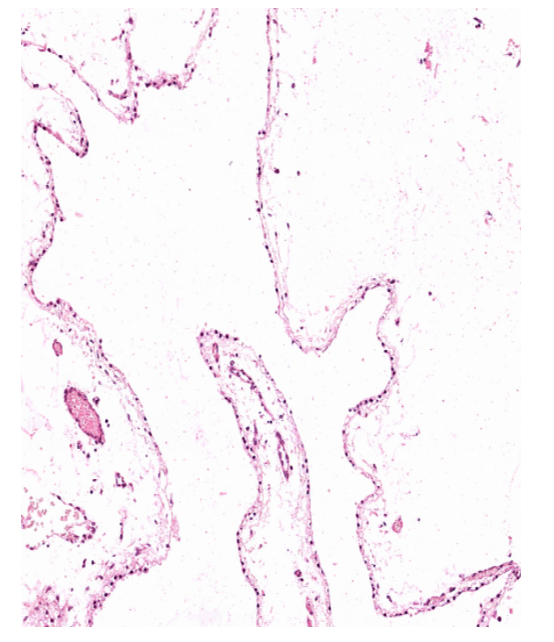

The patient was posted for surgery for L5-S1 discectomy with excision of cyst. At surgery a L1-L3 laminectomy was done. Careful durotomy of the bulging dura revealed a thin walled, oval shaped cyst of size 4.5x2x1 cm (Figure 4). Externally the surface was smooth. The cyst was removed enbloc. On opening, it was unilocular, fluctuant, transilluminant cyst containing clear fluid with a papery thin, transparent wall. Also, L5-S1 microscopic discectomy was done. Histological study of the operative specimen revealed a thin walled cyst lined by single layer of benign ciliated columnar cells. The wall showed loose connective tissue with no neural tissue (Figure 5). Analysis of the cyst fluid was similar with CSF. Patient was relieved of her symptoms in the immediate post operative period and was made ambulatory on the second post operative day. Two years post surgery, the patient is comfortable and completely relieved of her pain.

Figure 5: Microscopic view with HE staining of the cyst wall, showing cuboidal to columnar epithelium with absence of basement membrane.

These are thin walled cysts that are detached from the normal ependyma, ranging from 2–3 mm in diameter to up to 9 cm. The best diagnostic clue is there imaging features; they are thin walled with CSF like signal intensities in all pulse sequences. [5] These lesions may be indistinguishable from arachnoid cyst or choroid plexus cyst. On histological studies, neuroepithelial cysts are lined with simple columnar or cuboidal epithelium and absence of basement membrane. [1] [6] Electron microscopy can characterize ependymal cysts by presence of intercellular junction complexes, the absence of a basement membrane, membranebound granules in noncilliated cells, and absence of a coating on the luminal surface of the cells. [6] No mucinous production or glycoprotein can be detected by periodic acid-Schiff, alcian blue, mucicarmine staining. [7] Immunocytochemical stain can be useful in differential diagnosis of cystic lesion. [8] Wackym, et al. reported a spinal ependymal cyst which showed positivity for cytokeratin antibody reaction and negativity for glialfibrillary acidic protein and S-100. [7]